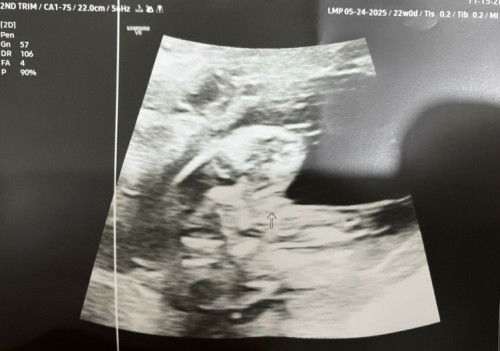

Is it Girl or Boy?

Hello anyone here mkakapagsabi anong gender ng baby ko. Nakalagay kasi 70% pa lang. 21 weeks preggy. Thank you!#askmommies #pregnacy